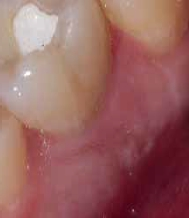

Bei der Diagnose des schmerzfreien Patienten stellte sich die beschriebene Erhebung schließlich als Fistel heraus (Abb. 1). Der Zahn 26 sowie die Nachbarzähne wurden zunächst einer Sensibilitätsprüfung unterzogen, wobei der Kältetest an Zahn 26 negativ ausfiel. Im Anschluss erfolgte dann die Anfertigung der diagnostischen Röntgenaufnahmen (Abb. 2 und 3). Dazu wurde ein Guttapercha-Stift in den Fistelgang eingebracht, um die Lokalisation der Entzündung zu erleichtern. Speziell bei der distal exzentrischen Aufnahme ließ sich dabei an 2 Wurzelspitzen des Zahns 26 die Entzündung ausmachen (Abb. 2). Insofern war in diesem Fall eine endodontische Behandlung des Zahnes angezeigt. Für diese wurde sogleich ein Folgetermin vereinbart.

Als sich der Patient immer noch schmerzfrei 4 Wochen später im Rahmen des Termins zur definitiven Versorgung in der Praxis vorstellte, war lediglich noch das Fistelmaul, aber keine Erhebung am Zahnfleisch mehr zu sehen (Abb. 4). Nachdem auch sonst keine Auffälligkeiten festzustellen waren, wurde wie geplant mit der endgültigen Versorgung des Zahnes 26 begonnen. Hierfür wurde zunächst eine Isolierung des Zahnes mit Kofferdam vorgenommen (Abb. 5). Für ein genaueres Bild vom Verlauf der Wurzelkanalanatomie lieferte eine Kontrastaufnahme mithilfe von K-Feilen und eines Silberstiftes, mb2, (Abb. 6) die notwendigen Informationen. Dabei stellte sich heraus, dass insbesondere einer der Kanäle sich durch eine außerordentliche Krümmung von beinahe 90° auszeichnete (Abb. 7).